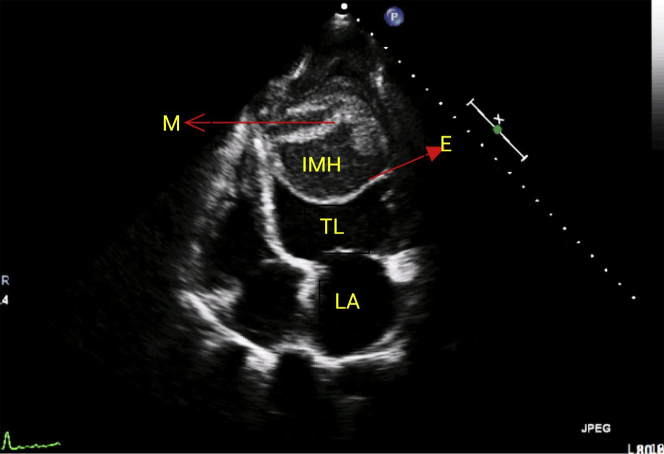

The electrocardiogram (ECG) showed sinus rhythm with right bundle branch block and low- voltage QRS complexes in limb leads and T inversion in V1 to V6 (Figure 1).Two-dimensional echocardiography showed left-ventricular (LV) dysfunction (ejection fraction [EF] ∼25%) with akinetic interventricular septum (IVS). There was a large intramyocardial dissecting hematoma (IDH) within the LV cavity, with a mobile endocardial flap (Figures 2, 3, 4, and 5, Videos 1, 2, 3, 4, 5, and 6). The 3-dimensional echocardiogram delineated the mobile endocardial flap and dissected myocardial flap clearly (Figure 6). The contrast (Definity, Lantheus Medical Imaging, North Bellerica, Massachusetts) echo opacified the true LV cavity, with no leak of contrast into the neocavity (Figure 7, Video 7). Cine magnetic resonance (MR) sequences confirmed the diagnosis of intramyocardial dissection with multiple layers of hematoma and thrombus (Figures 8 and 9, Videos 8 and 9).

Figure 2.

Parasternal Long-Axis View Showing Intramyocardial Hematoma

E = endocardial flap; IMH = intramyocardial hematoma; LA = left atrium; TL = true left-ventricular cavity.

Apical 4-Chamber View Showing the Hematoma With Dissected Myocardium

M = myocardial flap; other abbreviations as in Figure 2.